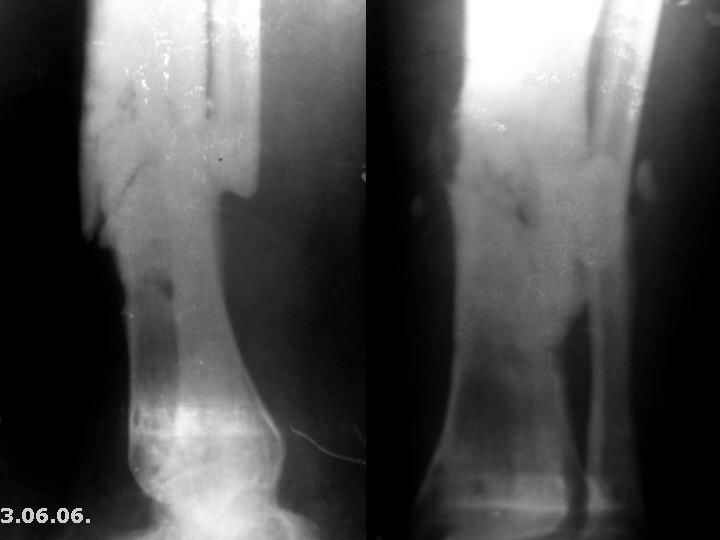

Мужчина, 29 лет. Состоит на лечении в ЦРБ. Диагноз: Замедленно сростающийся со смещением повторный перелом обеих костей левой голени в с/3-н/3, состояние после ВЧКО, хронический остеомиелит костей левой голени, свищевая форма, трофический синдром, смешанная контрактура левого коленного, голеностопного суставов.

Травма 20.12.04. - открытый 2Б тип, оскольчатый перелом обеих костей левой голени в с/3-н/3 со смещением отломков (ДТП). 20.12.04.- ВЧКО костей голени АВФ спице-стержневого типа, ПХО ран. Лечился амбулаторно. Перелом длительно не сростался. АВФ демонтирован 22.06.05., разрешена нагрузка на ногу, после чего появилась подвижность в области перелома. 8.07.05. - ВЧКО, туннелизация по Беку. Течение осложнилось развитием спицевого остеомиелита, 1.11.05. АВФ демонтирован, получал консервативное лечение. После нормализации состояния 17.11.05.- секвестрэктомия, ВЧКО голени. 12.04.06. АВФ демонтирован.

3.06.06.повторная травма - закрытый повторный перелом левой б/б кости в с/-н/3, лечился методом гипсовой иммобилизации.

Место болезни - ось голени искривлена. Kеллоидные рубцы в местах проведения спиц, по передней поверхности голени. По передней и внутренне-боковой поверхности голени в определяется 3 свища с умеренным серозным отделяемым. Отек голени и сустава, движения в коленном и голеностопном суставах ограничены, неврологических расстройств в стопе нет.